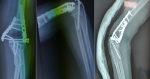

Dans la version originale de l´article, une erreur a eu lieu par inadvertance [1]. En effet, il s´agit d´une erreur concernant la Figure 6 qui montre un montage orthogonal utilisé pour l´ostéosynthèse d´une fracture de l´humérus distal (type C2 selon la classification de l´AO) par un abord trans-tricipital. Or, notre série a inclus uniquement les fractures traitées par voie postérieure trans-olécranienne. Nous avons joint la version corrigée de cette figure (Figure 1) qui montre un montage orthogonal pour une fracture de l´humérus distal opérée par voie postérieure trans-olécranienne et correspondant ainsi à la technique chirurgicale utilisée chez tous les patients de notre série. Cette erreur ne modifie en aucun cas le contenu ni la conclusion scientifique de notre article.

Figure 1: radiographie de contrôle post-opératoire montrant un montage orthogonal: une plaque postéro-latérale et une plaque médiale pour une fracture type C2